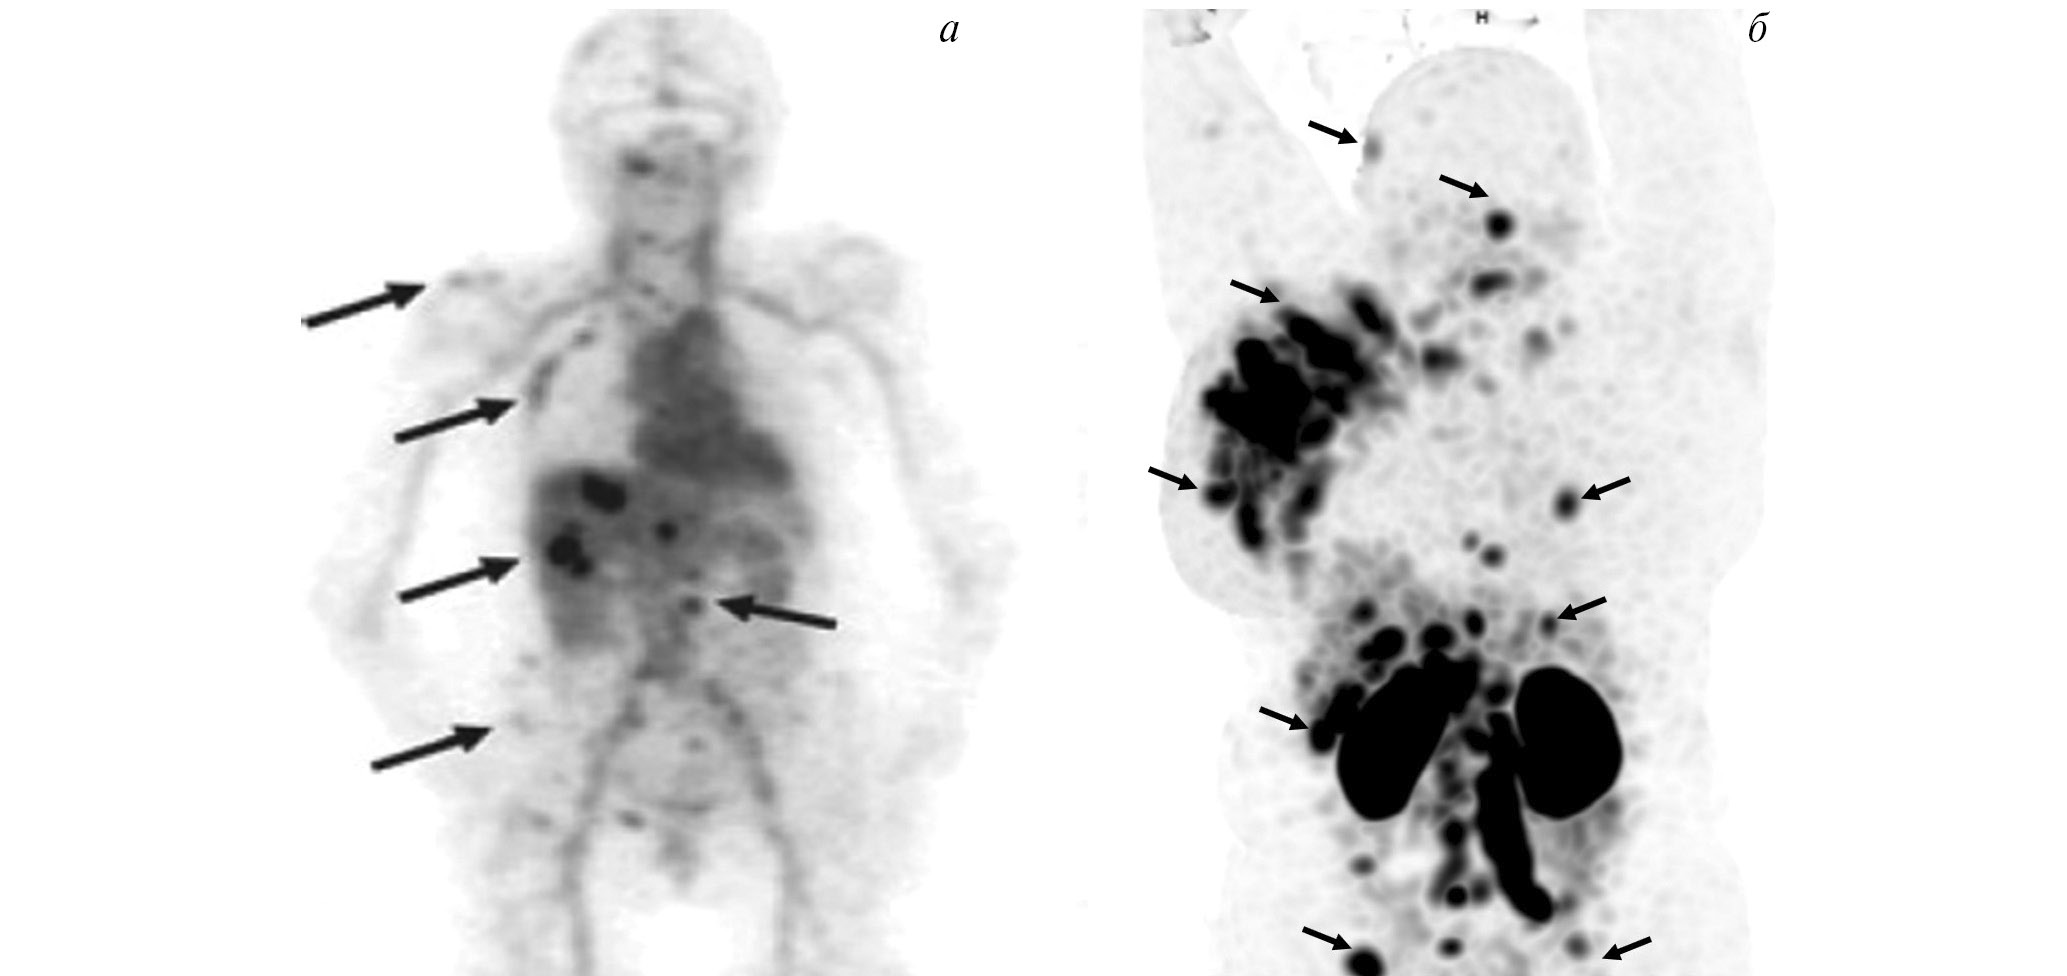

В рутинной клинической практике для ПЭТ/КТ-визуализации опухоли предстательной железы и её метастазов применяются радиофармпрепараты на основе простатспецифических мембранных антигенов, меченных 68Ga ([68Ga]Ga-ПСМА-11, [68Ga]Ga-ПСМА-617, [68Ga]Ga-ПСМА-I&T) либо 18F ([18F]F-DCFPyL, [18F]F-ПСМА-1007) [22, 23]. Главные преимущества меченных 99mТс препаратов, тропных к ПСМА, — невысокая стоимость и доступность технеция-99m, а также возможность визуализации опухоли с помощью гамма-камеры. В настоящее время для этих целей предложен ряд радиофармпрепаратов [24]. В России зарегистрированы наборы для приготовления 99mTc-HYNIC-ПСМА (“ПСМА HYNIC, 99mТс”, Польша; “Проскан, 99mТс”, Россия). Отечественный РФЛП разрабатывался в ТПУ и НИИ онкологии Томского НИМЦ. Клинические испытания 99mТс-ПСМА показали его высокую эффективность при диагностике и стадировании рака простаты, а также при отборе на радиолигандную терапию и оценке её воздействия (рис. 4).

Рис. 4. ОФЭКТ с 99mТс-ПСМА пациента с раком простаты до (а) и после (б) четырёх курсов радиолигандной терапии 177Lu-ПСМА

Показания к радионуклидной диагностике с указанными выше препаратами — стадирование рака предстательной железы до начала лечения (хирургического вмешательства или лучевой терапии) [25] и диагностика рецидива опухоли после радикального лечения [25]. Кроме того, радиофармпрепараты на основе ПСМА участвуют в отборе пациентов с метастатическим кастрационно-резистентным раком предстательной железы на ПСМА-направленную радиолигандную терапию. Такая визуализация необходима для определения наличия и интенсивности гиперэкспрессии простатспецифического мембранного антигена в потенциальных мишенях для радионуклидной терапии [26].

Опубликовано множество работ, сообщающих о высокой эффективности радионуклидной терапии с 177Lu-ПСМА-617 (Pluvicto, Novartis) у пациентов с метастатическим кастрационно-резистентным раком предстательной железы. В частности, в многоцентровом исследовании “Vision” показано, что препарат 177Lu-ПСМА-617, по сравнению с традиционным лечением, позволяет повысить выживаемость без прогрессирования (с 3.4 до 8.7 месяцев) и общую выживаемость (с 11.3 до 15.3 месяцев) пациентов с данным заболеванием [27]. Для лечения метастатического рака предстательной железы также перспективен 225Ac-ПСМА. Он продемонстрировал эффективность при лечении больных, получивших заметные миелотоксические осложнения после предыдущих курсов с 177Lu-ПСМА либо вовсе не показавших положительной динамики [28].